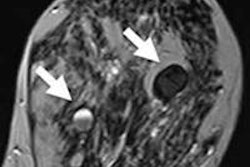

Ovarian tumors are complicated and aggressive, and for patients with suspected tumors, the most important factor for survival is stage at diagnosis.

Researchers from Belgium have crafted a model that helps with just that. The assessment of different neoplasias in the adnexa model contains three clinical and six ultrasound predictors: age, serum CA-125 level, type of center, maximum diameter of lesion, proportion of solid tissue, more than 10 cystic locules, number of papillary projections, acoustic shadows, and ascites. What predictor is the most telling? And how well does the model work? Find out here.

Dutch researchers believe they have confirmed the accuracy and safety of a new sentinel node procedure that injects radiotracers in ligaments of women with epithelial ovarian cancer, helping them avoid more invasive, radical surgery.